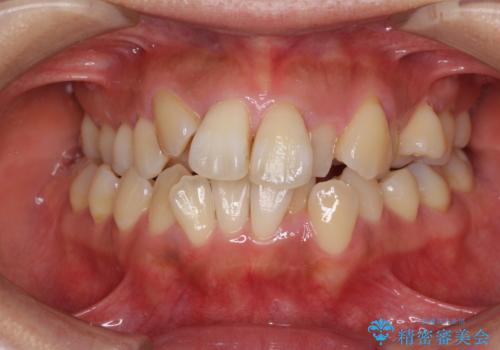

- 上顎の著しい叢生と奥歯の咬みにくさを気にして来院された患者様です。

骨格的に上顎は狭く、下顎は右側にシフトしていたため、右側臼歯はクロスバイトとなっていました。